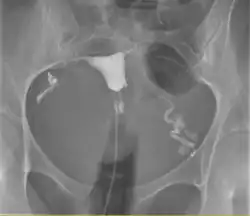

Histerossalpingografia

Histerosalpingografia é um exame de raio-x do útero e das trompas uterinas, com a utilização de contraste iodado que é injetado no interior do útero através de uma cânula. Serve para diagnosticar malformações, doenças da cavidade uterina e do interior das trompas. Sua principal indicação está correlacionada com a infertilidade e é o melhor método[carece de fontes] para diagnosticar obstrução das trompas.